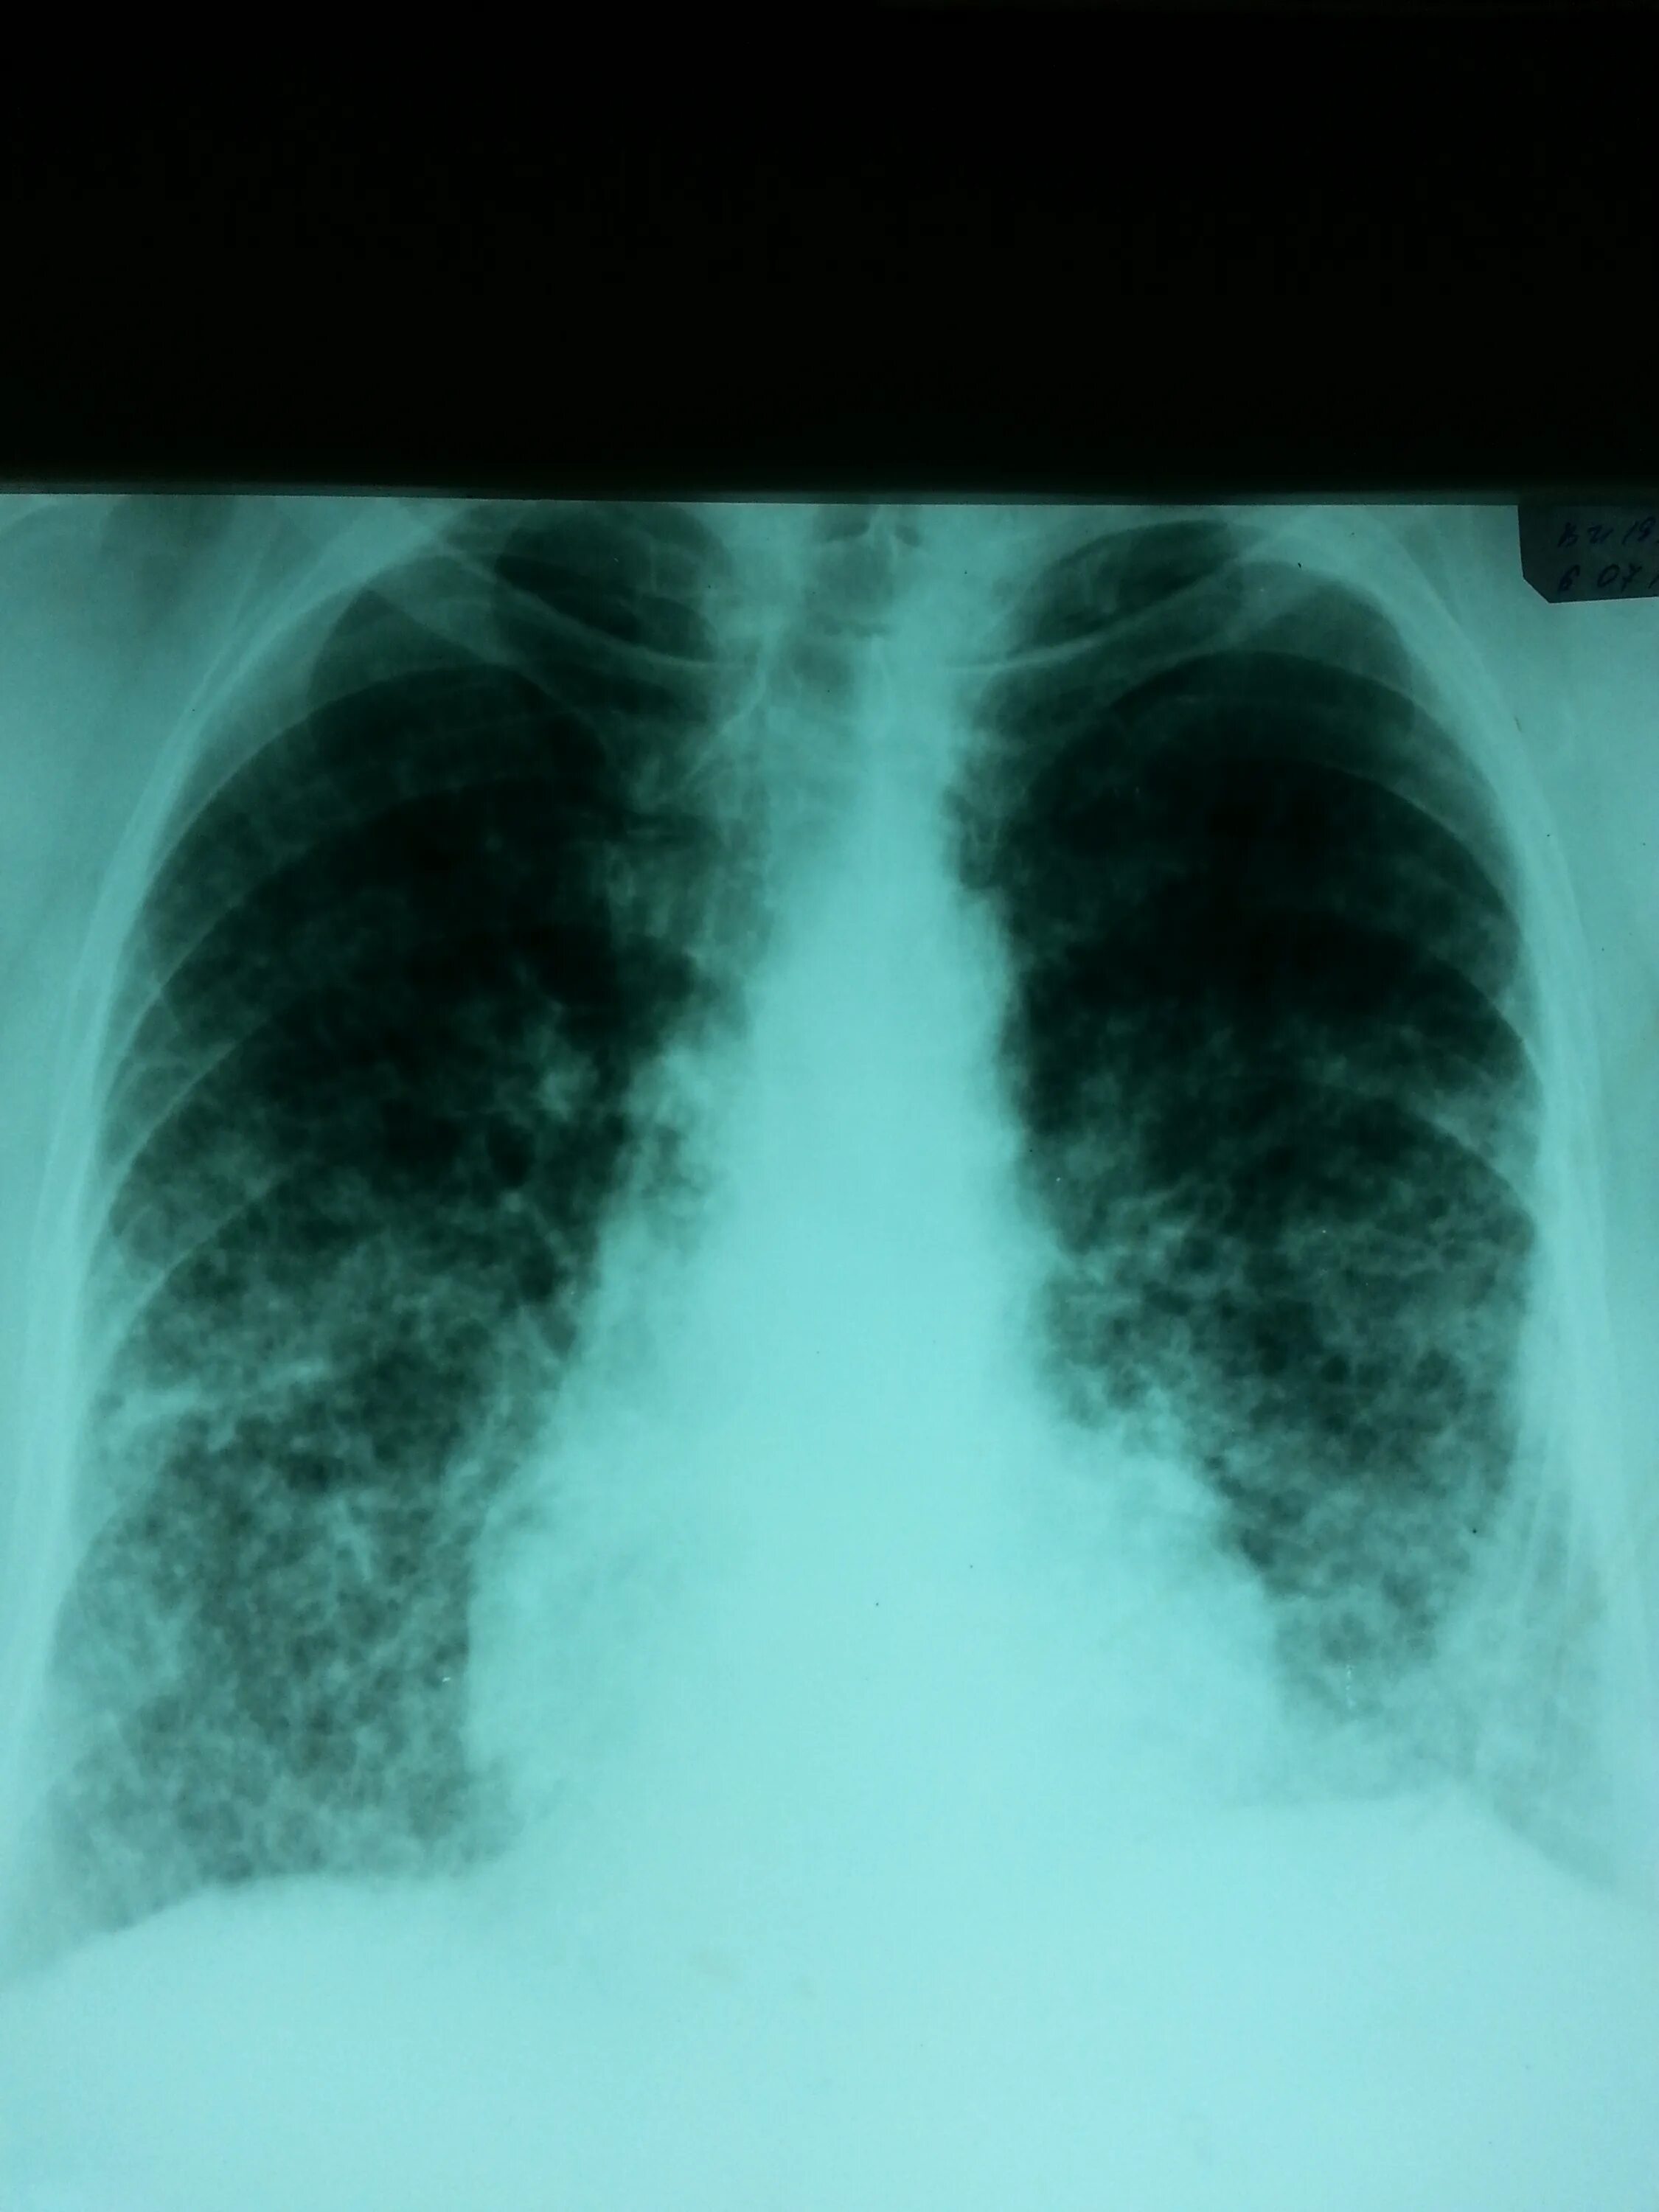

Пневмосклероз рентгенограмма